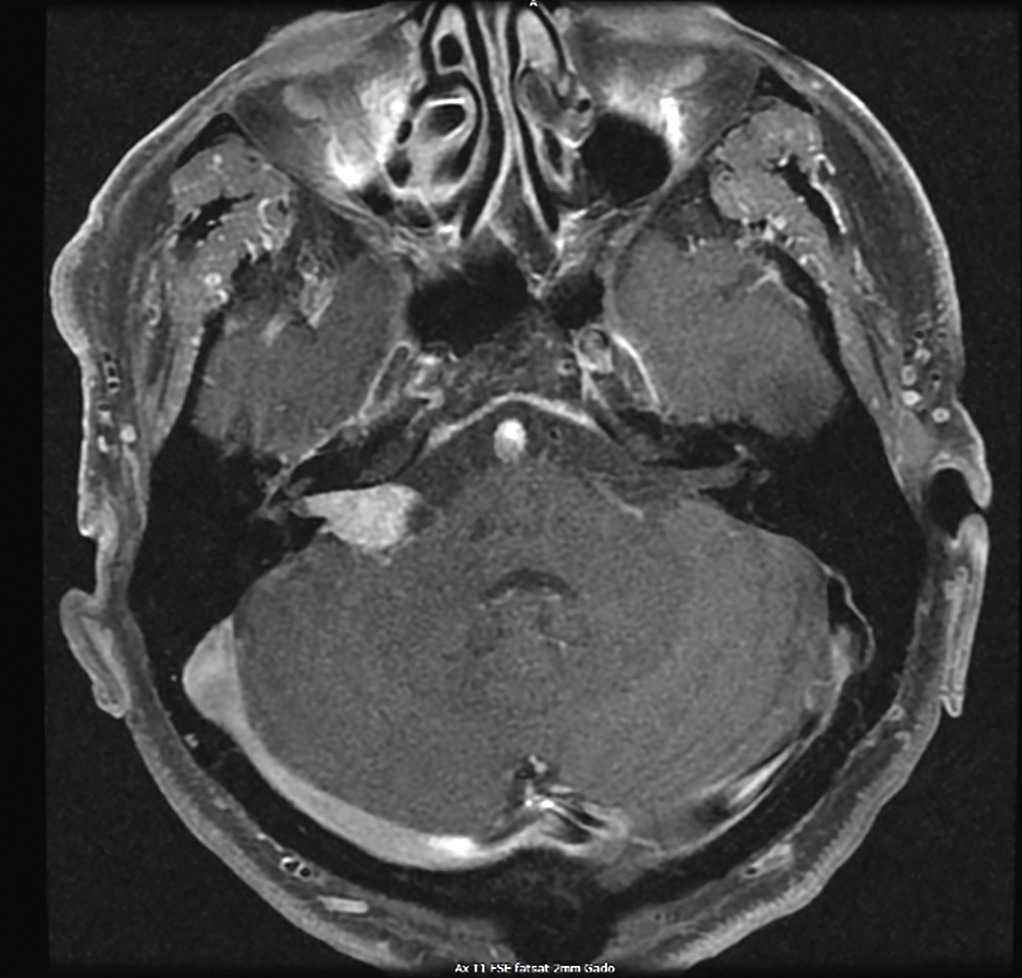

Siège volontiers dans le conduit auditif interne et croît vers l’angle ponto-cérébelleux (APC). D’où atteinte des fonctions vestibulaires et auditives.

L’IRM a amélioré la détection des schwannomes de petite taille (70 % des cas au diagnostic).

Examen le plus sensible pour apprécier la stabilité ou l’évolution de la tumeur.